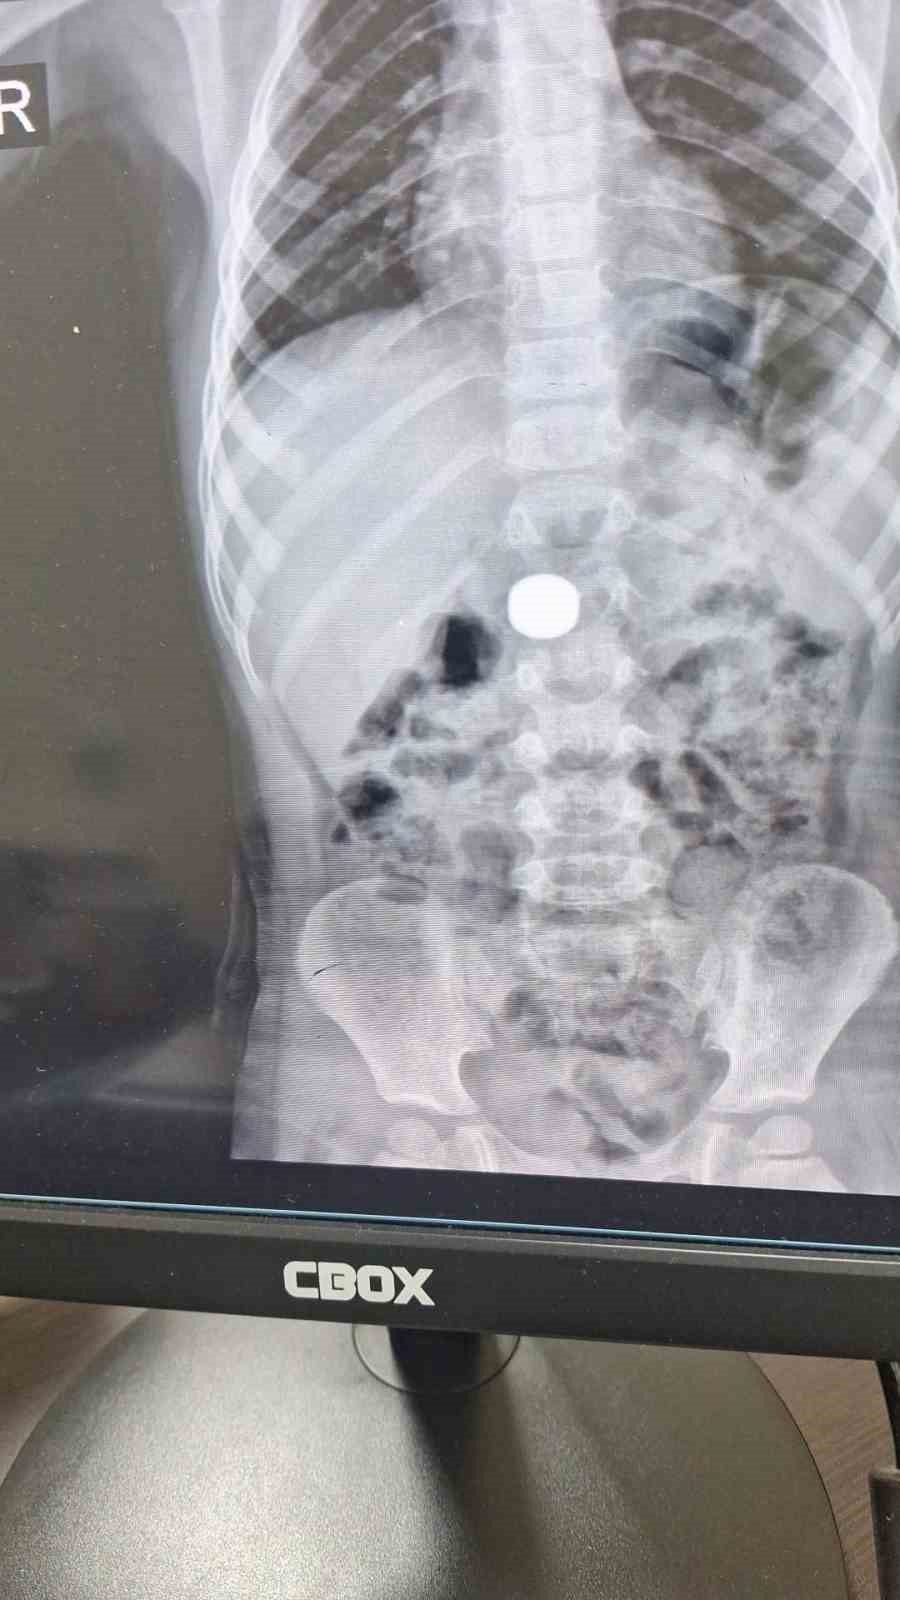

Karaman’da 4 yaşındaki İ.K.’nin mıknatıs yuttuğundan şüphelenen ailesi, Karaman Eğitim ve Araştırma Hastanesi Acil Servisi’ne başvurdu. Yapılan tetkiklerde çocuğun ince bağırsağında iki adet mıknatıs bulunduğu tespit edildi. Gözlem altına alınan çocuğun sağlık durumu 5 gün boyunca takip edildi. Çocuk Cerrahisi Uzmanı Doç. Dr. Mehmet Uysal’ın gerçekleştirdiği operasyonla bağırsakta tıkanıklığa yol açan iki mıknatıs başarılı bir şekilde çıkarıldı.

Hastayı 5 gün boyunca takibe aldıklarını belirten Doç. Dr. Mehmet Uysal, gözetim süresince çekilen filmlerde mıknatısların yer değiştirmediğini söyledi. Uysal, “Hastayı genel anestezi altında ameliyata aldık. İnce bağırsakta iki mıknatısın birbirine yapışık halde olduğunu gördük. Gerçekleştirdiğimiz operasyonla mıknatısları çıkardık. Ameliyat sonrası hastamız üçüncü gününde taburcu edildi. Şu an genel durumu iyi” dedi.